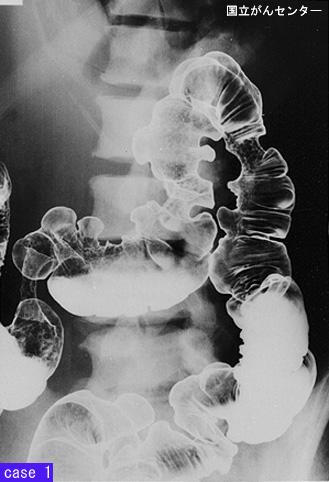

疾病(病理主体)的分类转移性肿瘤/

部位(按器官分)大肠/占据大肠的2个以上区域

检查方法X线

肿瘤最大直径40以上